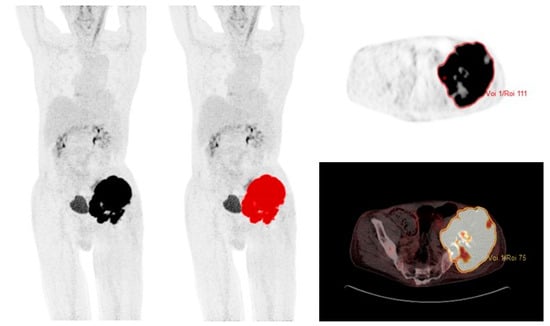

2.3. 18F-FDG PET/CT

3.4. PET Parameters, Survival, and Metastatic Disease